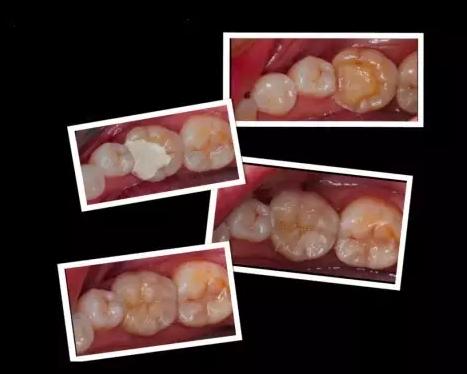

嵌体和传统的补牙不同之处是:嵌体是在口外石膏模型上由专门的牙科技师制作出来的,然后再由临床医生将其戴入患者口内,最终粘固形成的。

1、因为它的整个制作过程是在口外完成的,所以它还可以很好的恢复原来牙齿的外形,恢复原来牙齿的咀嚼效率。而这一点,是传统补牙无论如何都无法比拟的。

2、嵌体的整个的制作过程中完全避免了在口腔内部操作的干扰因素。这就使得嵌体的制作比传统的补牙要更精细。技师在制作嵌体的时候,会控制它与牙体的弥合程度,这样就尽可能的避免了牙齿在日后的使用中再次出现龋坏。

这些嵌体,在最终戴如患者口内的时候,真是的非常的完美。在使用上没有任何的影响和不适,而且坚固耐用。做嵌体修复的时候,好的材质也对嵌体的修复效果产生影响。